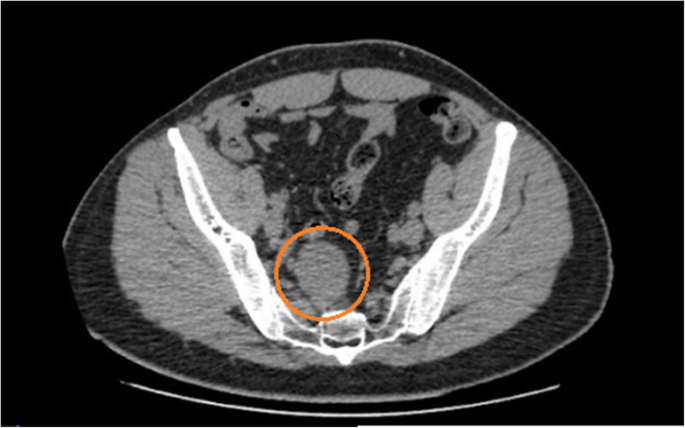

A 41 year old male presented at the emergency room reporting abdominal pain in the hypogastric region and in the lower right limb with neurogenic characteristics (paresthesia and burning mainly in the L2 dermatome) one week prior to admission. The patient had a history of papilliferous tumor of the thyroid, resected two years previously without need for complementary therapy. The patient underwent computerized tomography (CT) of the abdomen (Figs. 1 and 2), which revealed a hypodense and circumscript nodular formation, located in the right median presacral region, at the level of vertebrae S1 and S2, measuring approximately 4.4 × 3.9 × 3.4 cm. There were no other abdominal abnormalities. The decision to perform an excision surgery was based on the symptoms (associated with the topography of the tumor) and the need of diagnosis since the CT was inconclusive. There was no suspicious diagnosis related to the previous tumor.